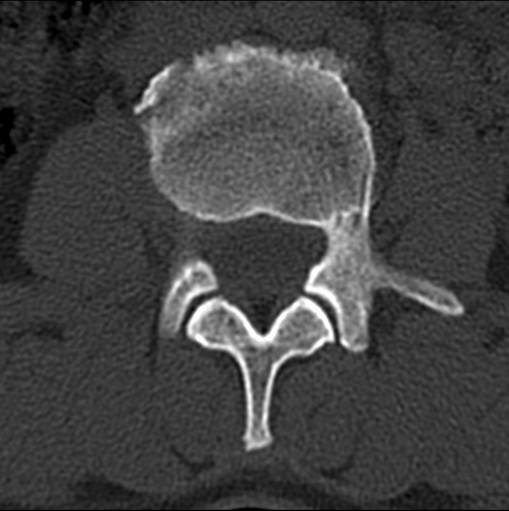

女、49、腰外伤请会诊,是永纯骨骺还是骨折,新鲜还是陈旧。如何鉴别?

支持椎缘骨.引用::椎缘骨(vertebral anterior marginal cartilage node)在腰椎影像检查中经常会遇到,多见于椎体前上角,次为前下角,偶见于后上角,罕有发生于椎体侧缘者。发病机制学说不一,包括外伤、永存骨骺及椎间盘突出等学说。以后者最多见,椎体软骨板和(或)椎体骨骺交界处存在薄弱区,在异常外力的作用下诱发髓核突出,使得椎体骨骺与椎体分离,形成三角形骨块。

不能再叫永存骨骺,只有发生在椎体前缘是椎缘骨,而发生椎体后缘叫椎体后缘骨内软骨节结。